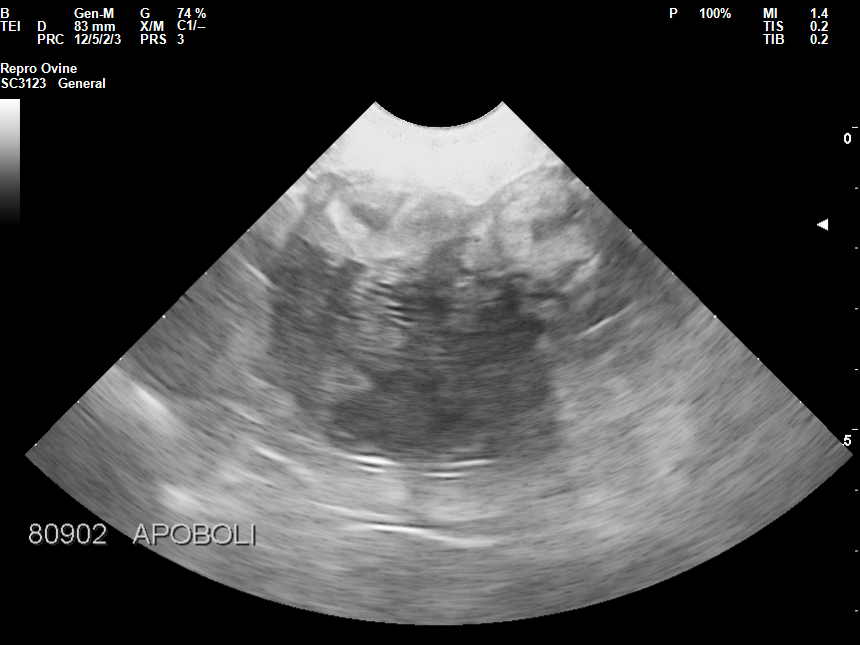

• Διάγνωση εγκυμοσύνης

• Διάγνωση πολυδυμίας

• Διάγνωση παθολογικών καταστάσεων μήτρας